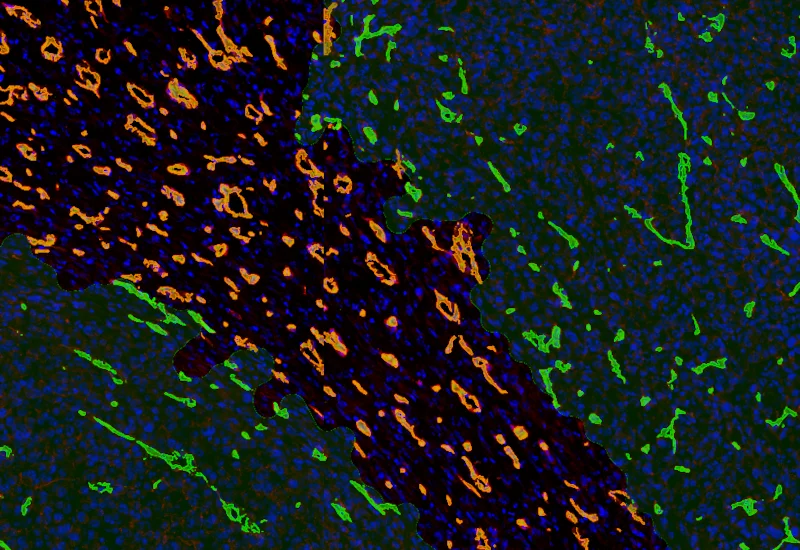

The Angio Sirius Red App detects collagen based on Sirius Red staining as well as blood vessels. As outcome the APP outputs the area of Sirius Red stained collagen as well as the number of detected vessels.

vessel detection

Collagen detection

IF Tumor Vascularization

Segment tissue into tumor and stroma/healthy areas, detect CD31+ vessels, and quantify vessel number, area, density, and connectivity with configurable wall closing and distance linking.

vasculatization, cancer, stroma, tumor, blood vessels, CD31, spatial analysis, tumor microenvironment